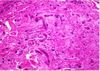

What is this lesion?

Dedifferentiated chondrosarcoma ## Footnote The histology pic shows a cartilaginous tumor juxtaposed to a high grade sarcoma This gross lesion is showing blue/grey cartilage tumor juxtaposed to a fleshy, tan/white sarcomatous tumor. Variable amounts of 2 components so careful sampling!